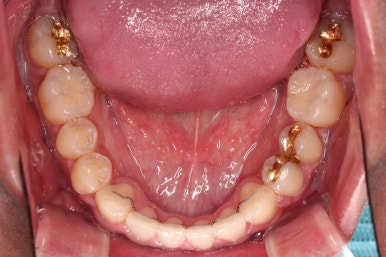

초진 시 입안의 모습입니다.

비교적 고른 편이긴 하나 아랫니가 전반적으로 밀려 나오면서 앞니끼리 부딪혀 있는 양상이고요.

어금니 맞물림도 긴밀하게 톱니바퀴처럼 위아래가 맞물려 있는게 아니라 엉성한 모습이죠.

앵글씨 3급 부정교합이라고 하는데요.